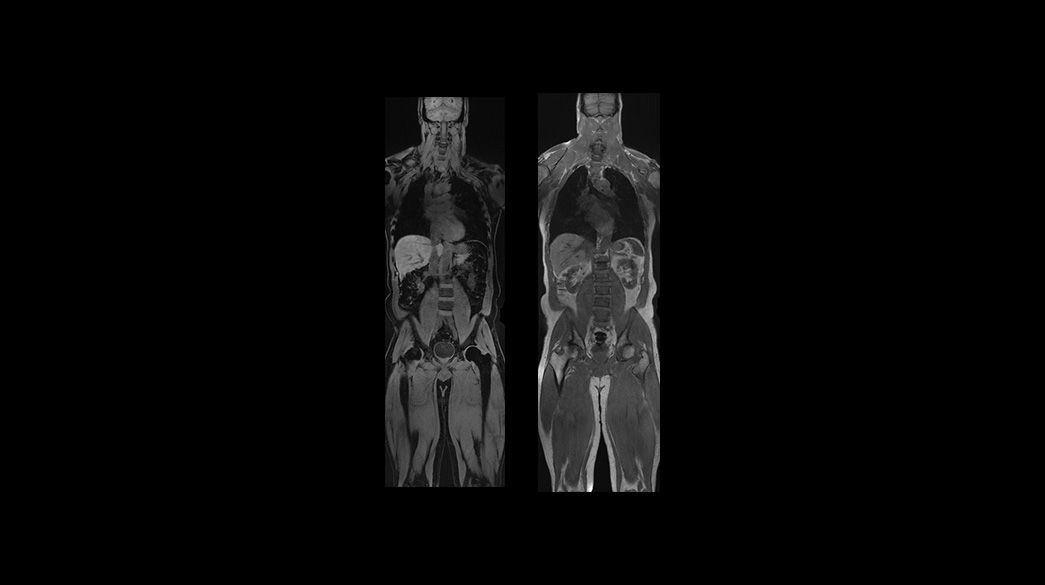

Oncology MRI for SIGNA™

Oncology MR imaging techniques to capture anatomical and morphological data with robust tissue contrast, motion-insensitive and high temporal and spatial resolution for oncological assessment.

Clinical Oncology

Oncological MRI imaging applications